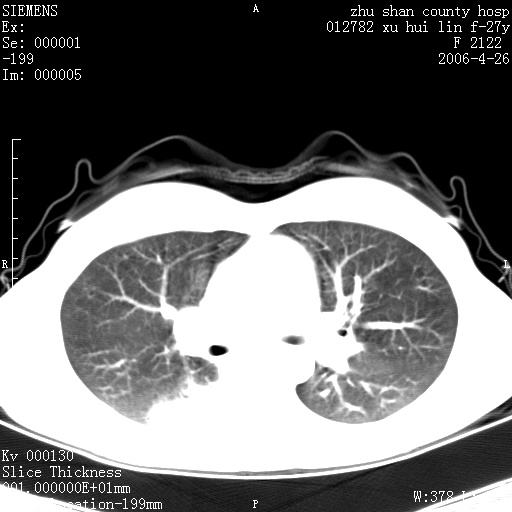

女性 病人 27岁!本院职工家属,五月前因感冒透视发现病变,ct示:左肺下叶背段感染性病变。经过半月规范抗生素治疗后复查病变无明显变化,后行四月规范抗痨治疗,复查无明显变化,后复查无效!请大家帮忙看看!

右肺下叶背段见片状高密度区,边界不清,密度不均,无钙化及空洞影,背段支气管通畅。所见层面肺门及纵隔内未见明显肿大淋巴结影。

女性 病人 27岁!本院职工家属,五月前因感冒透视发现病变,ct示:左肺下叶背段感染性病变。经过半月规范抗生素治疗后复查病变无明显变化,后行四月规范抗痨治疗,复查无明显变化,后复查无效!

诊断:首先还是考虑为慢性炎症。

结核虽然好发于下叶背段,但周围无明显卫星灶,化验结果怎样?